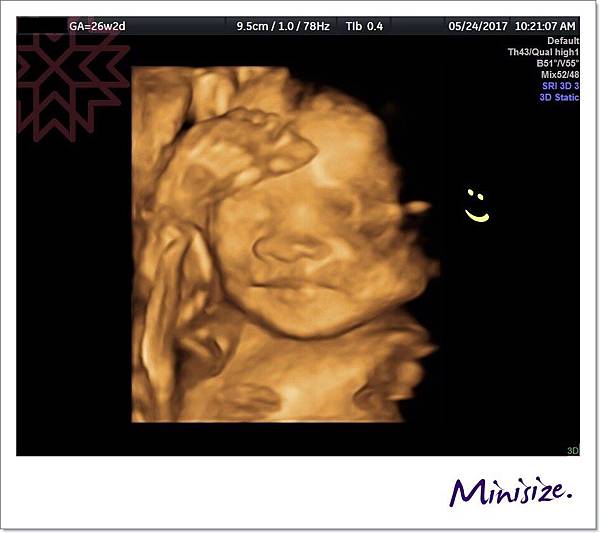

最後 分享一件趣事

產檢當天 Timo寶寶很害羞

不是把臉蛋兒藏起來

就是把軟Q地腳腳擺頭上

即使是醫生用力搖他 也不願意放下來

麻麻實在是太好奇Timo寶寶長相

當下與醫生一起向小寶貝精神喊話

我們就捕捉到這張可愛的表情

Timo寶寶靦腆的一抹微笑 ![]()

大家都融化了